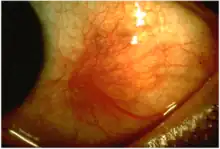

In this picture, the eyeball shows a large red inflamed spot on its sclera, a symptom of scleritis, just left of the iris.

Scleritis is a serious inflammatory disease that affects the white outer coating of the eye, known as the sclera. The disease is often contracted through association with other diseases of the body, such as granulomatosis with polyangiitis or rheumatoid arthritis. There are three types of scleritis: diffuse scleritis (the most common), nodular scleritis, and necrotizing scleritis (the most severe). Scleritis may be the first symptom of onset of connective tissue disease.[1]